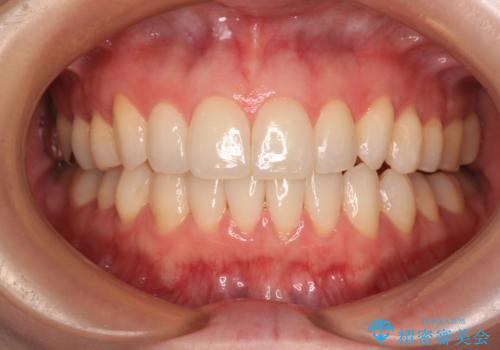

上下の八重歯とクロスバイト ワイヤー装置での抜歯矯正

前歯の歯列が整ったことで、歯磨きが大変やりやすくなり、患者様には大変満足していただけました。